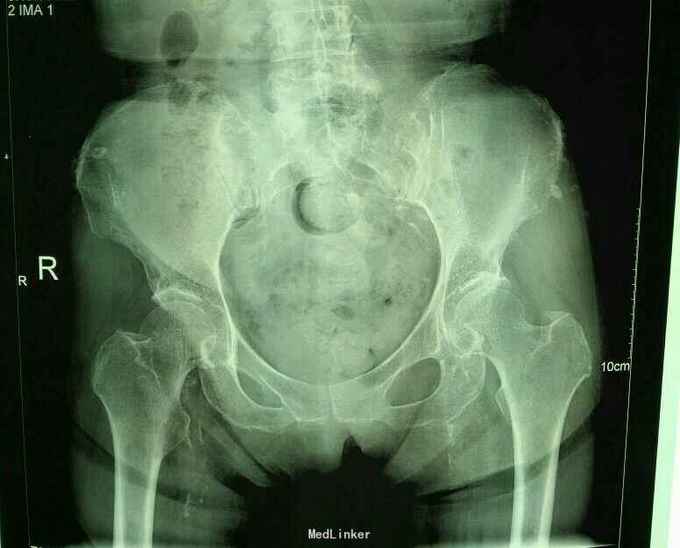

主诉:外伤致右髋部疼痛、活动受限12小时余 现病史:患者自述于12小时前因外伤伤及右髋部,当即感疼痛、活动受限,于A医院检查示右股骨颈骨折,为求进一步治疗,遂来我院就诊,以右股骨颈骨折收入院。入院时患者神志清,精神可,各项生命体征平稳,无发热,无头痛、头晕,无恶心、呕吐,无咳嗽、咳痰,纳眠可,二便调。 专科检查:脊柱生理弯曲存在,右髋部肿胀,右下肢屈曲外旋缩短畸形,右腹股沟中点处压痛(+),右足跟叩击痛(+),右髋部活动功能受限。肢端感觉、血运及活动可。 辅助检查:股骨颈椎病骨质连续性中断,断端嵌插缩短,颈干角变小。 术前及术后片子

专科检查:脊柱生理弯曲存在,右髋部肿胀,右下肢屈曲外旋缩短畸形,右腹股沟中点处压痛(+),右足跟叩击痛(+),右髋部活动功能受限。肢端感觉、血运及活动可。 辅助检查:股骨颈椎病骨质连续性中断,断端嵌插缩短,颈干角变小。

右股骨颈骨折 完善相关检查后行右股骨颈骨折股骨头置换术。